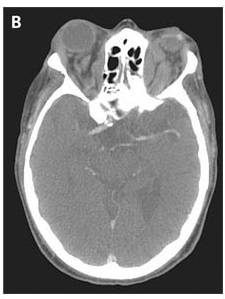

Computed tomography of the head showed orbital masses that followed the contour of the orbit and did not cause bony erosion (image below).